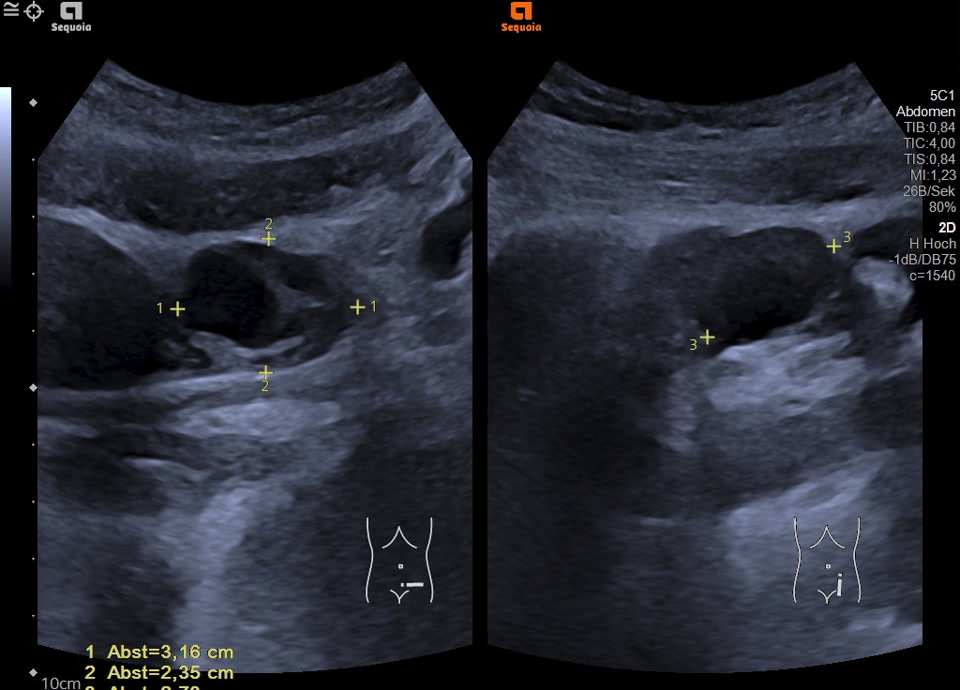

• Enlarged mulitcystic ovar